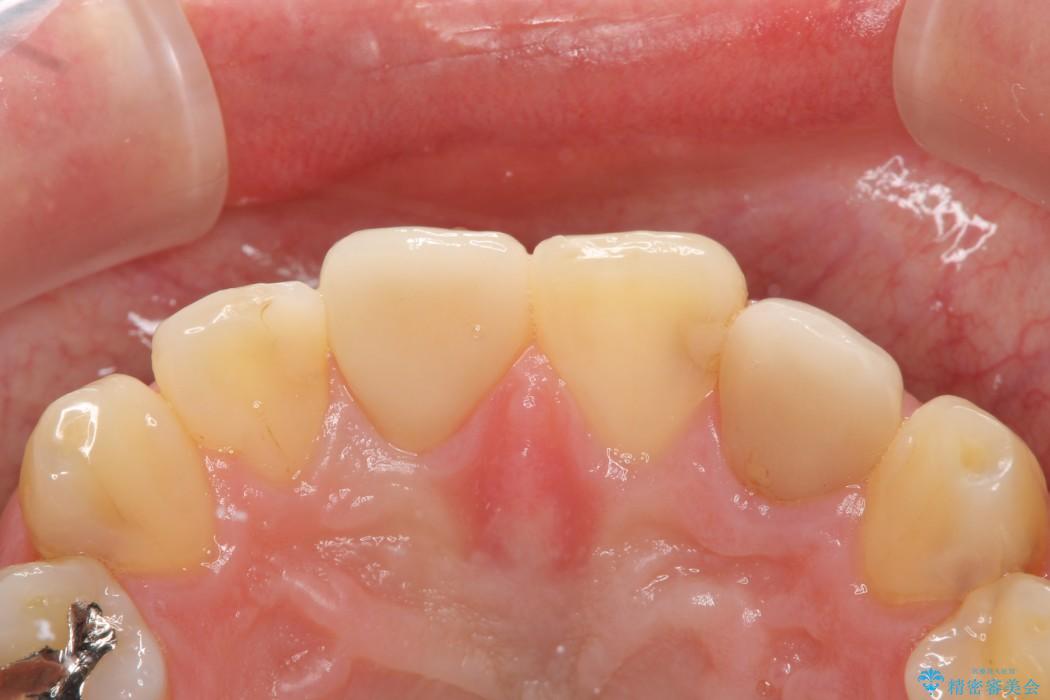

治療後について

今回のケースでは丁寧に虫歯を取りきることにより、神経を保存することができました。